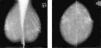

Patrones mamográficos del parénquima glandularSe asignará una categoría de patrón mamográfico en todas las lecturas, independientemente de que el resultado final sea normal o se describa algún tipo de hallazgo. Se consideran 4 categorías según el sistema BI-RADS. (fig. 1):

Grasa: mama de composición predominante grasa.

Densidad media: mama con tejido fibroglandular disperso.

Heterogénea: mama con tejido glandular heterogéneamente denso.

Densa: mama con parénquima glandular extremadamente denso que puede ocultar lesiones.